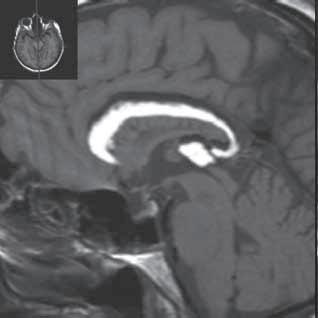

I.1.8 Dandy-Walkerova malformace (D-W variant, D-W komplex, D-W spektrum )

V současné odborné literatuře je nejčastěji užíván termín D-W spektrum, který snad nejlépe vyjadřuje velmi široké možnosti vrozených změn zadní jámy lební. Mezi tuto skupinu cystických malformací zadní jámy lební pak řadíme klasickou malformaci D-W a její varianty, mega cisterna magna, arachnoidální cystu zadní jámy lební a retrocerebelární vak (Blake’s pouch cysta). Zařazení malformace do určité klinické jednotky není někdy jednoznačné, proto je možná výhodnější a přesnější vycházet z přesného popisu zobrazených změn. Příčina D-W malformace není známa, nabízejí se dvě hypotézy: 1. nepropustná spodina IV. komory, eventuálně uzávěr nebo pozdní otevření otvorů, kterými proudí likvor ze IV. komory. 2. primární hypogeneze mozečku. Embryonální vývoj mozečku ze všech hlavních struktur mozku trvá nejdelší dobu, a proto je velmi vulnerabilní k různým patologickým příčinám po dlouhou dobu svého vývoje.

Zobrazení

D-W malformace je charakterizována hypoplazií vermis mozečku, rozšířením IV. mozkové komory, která se často cysticky vyklenuje dorzálně a může imitovat arachnoidální cystu, rozšířením zadní jámy lební a vysokým úponem tentoria s confluens sinum nad lambdovým švem. Okcipitální kost může být vlivem tlakových změn remodelována, existují i případy s porušením její kontinuity a encefalokélou. Hydrocefalus pozorujeme v 80 %, častá je přítomnost dysgeneze corpus callosum, schizencefalie.

D-W variant byl vyčleněn pro případy, kdy všechny základní příznaky nemusí být plně vyjádřeny nebo může některý zcela chybět. Bývá přítomna hypoplazie mozečku, což je dominantní příznak, IV. komora je obvykle rozšířena, někdy pozorujeme, že tvarem připomíná na axiální řezu „klíčovou dírku“, zadní jáma lební naopak rozšířena nebývá.

Mega cisterna magna je struktura likvorového signálu, lokalizována dorzálně a kaudálně od mozečku, není doprovázena hypoplazií mozečku, rozšířením IV. komory ani hydrocefalem, někdy může být tlakem zeslabená lamina interna lebky v zadní jámě lební. Diferenciální diagnostika mezi mega cisterna magna a arachnoidální cystou je mnohdy obtížná a může nám pomoci CT cisternografie (chybí nebo pozdní pronikání kontrastní látky do arachnoidální cisterny), určité informace může přinést MR vyšetření pulzace likvoru.

Retrocerebelární vak (Blake’s pouch cysta) vzniká embryonálně vyklenutím části stropu IV. komory (velum

mediale superius) do cisterny magna (vak je vyplněn likvorem, chybí foramen Magendii). Je charakterizován rozšířenou a široce otevřenou IV. komorou, která komprimuje bazální cisterny, hypoplazie vermis mozečku naopak není přítomna. Široce komunikující IV. komora (někdy obsahuje choroidální plexus), přičemž komunikace mezi komorovým systémem a subarachnoidálními prostory je pouze přes laterální foramina Luschkae.

Obr. I.1.8a Dandy-Walkerova malformace, rozšířená IV komora (tvar klíčové dírky)

Obr. I.1.8b Dandy-Walkerova malformace, rozšířená IV komora široce komunikující s cisterna magna, hypotrofie mozečku (snímky zapůjčeny z archivu prim doc MUDr M Mechla, Ph D, MBA)

Obr. I.1.8c Dandy-Walkerova malformace, rozšířená IV komora široce komunikující s cisterna magna, hypotrofie mozečku (snímky zapůjčeny z archivu prim doc MUDr M Mechla, Ph D, MBA); stejný pacient jako na obr I 1 8b

Obr. I.1.8d Dandy-Walkerova malformace, rozšířená IV komora široce komunikující s cisterna magna, hypotrofie mozečku, vysoký úpon tentoria (šipka) (snímky zapůjčeny z archivu prim doc MUDr M Mechla, Ph D, MBA); stejný pacient jako na obr I 1 8b, c

Obr. I.1.8e Dandy-Walkerovo spektrum (hypoplazie vermis, IV komora je rozšířená a široce zeje) (snímky zapůjčeny z archivu as MUDr J Lisého, CSc )

Obr. I.1.8f Dandy-Walkerovo spektrum (hypoplazie vermis, IV komora je rozšířená a široce zeje) (snímky zapůjčeny z archivu as MUDr J Lisého, CSc ); stejný pacient jako na obr I 1 8e

Obr. I.1.8g Dandy-Walkerovo spektrum (hypoplazie vermis, IV komora je rozšířená a široce zeje), (snímky zapůjčeny z archivu as MUDr J Lisého, CSc ); stejný pacient jako na obr I 1 8e, f

Obr. I.1.8h Mega cisterna magna

Obr. I.1.8ch Retrocerebelární vak (Blake’s pouch cyst), široce komunikující IV komora, chybí foramen Magendii